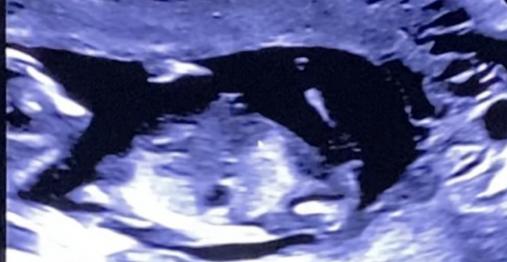

Tricky NUB 13+1 weeks? Long NUB but some stacking?

I had a scan yesterday (13+1 weeks!). During the scan I was convinced I saw long somewhat flat, but also a stacked nub (I saw a shadow in the background), but the tech said it was the stacking was the umbilical cord. The tech said she saw a flat NUB that I is why she was leaning more towards girl.

I posted my scans online and got mostly boy guesses (some girl because of the "flat" NUB) but I was wondering if it's still possible it might be a girl? That the "stacked thing" is something else??? (Already got 3 boys so a girl would be so welcome!)